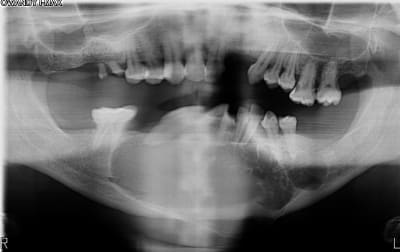

J'en ai déjà eu 3 comme ça, originaires de pays de l'est voir de l’extrême-est.

Un père pour un trou de 48 à 36 et son fils autour d'une 43 incluse. (origine génétique ?)

Et un autre au niveau latéral doit.

Idem adressé au CHU le plus proche.

Bon je sais , ça fait un peu le concours de celui qui à le plus gros ... kyste !!

Qui dit mieux ?